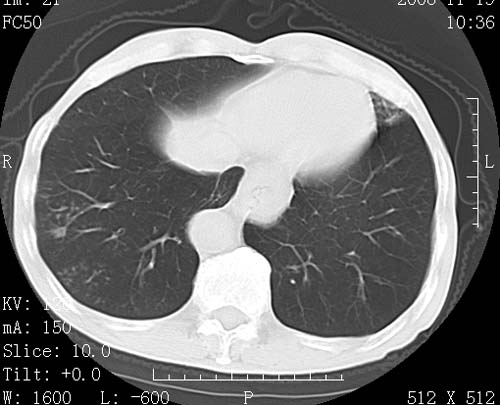

标题: CT16691:m 67 胃镜确诊食管下段及贲门癌 [打印本页]

标题: CT16691:m 67 胃镜确诊食管下段及贲门癌

术前查体,双肺部结节是转移?结核?请点评

1)符合食管癌表现。2)两肺及纵隔淋巴结多发性转移瘤。3)左肺上叶舌段及两肺下叶炎症感染。

1)符合食管癌表现。2)两肺及纵隔淋巴结多发性转移瘤。3)左肺上叶舌段支气管扩张伴感染.

食管癌伴双肺转移,评述:肺部毛细血管网丰富,全身血液均快速流经肺部,癌细胞容易过滤定植,形成转移瘤,影象特点为以毛细血管末梢为中心的结节灶,边缘光滑锐利,少见有中心空洞着,不同来源的转移瘤可有各自特点,如甲状腺癌为双肺弥漫性微结节,本例有原发灶,双肺影象灶典型,左肺舌段条带状网格样伴胸膜天幕征,可视为癌性淋巴管炎。

符合食管癌表现。两肺及纵隔淋巴结多发性转移瘤。双肺还有支扩表现.